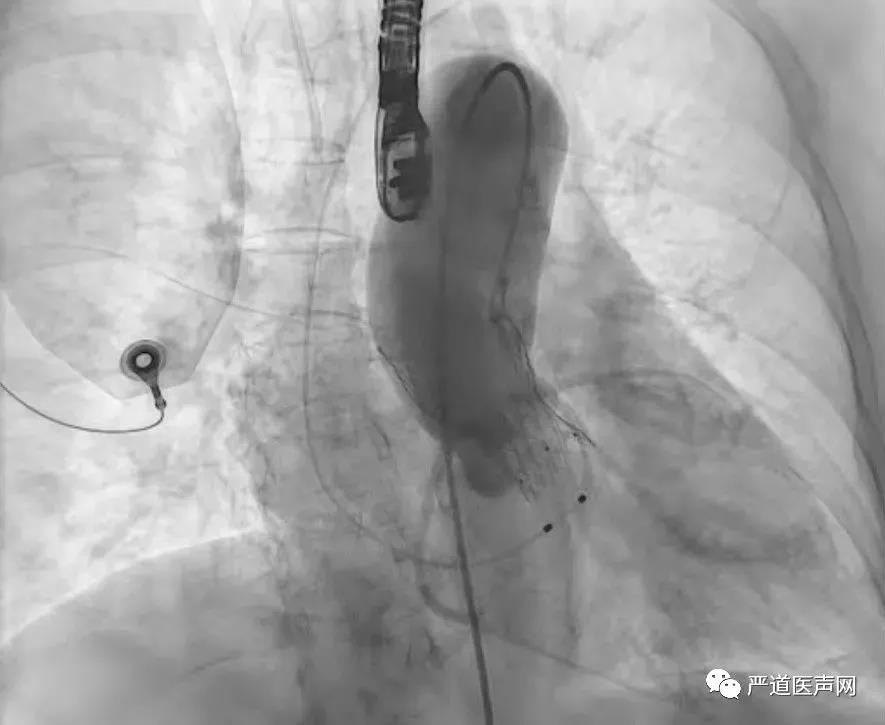

手术由周达新教授主刀,为确保手术成功,德达心外科手术团队同时在现场做好开胸准备。由于患者瓣膜钙化严重,术中主动脉瓣球囊扩张后出现血压不稳,手术团队在数分钟内迅速且准确定位释放人工主动脉瓣膜支架并行二次球囊扩张。复查主动脉根部造影及经食道心超均提示植入瓣膜开合良好,微量返流,测量跨瓣压差<10mmHg,手术最终取得了满意的效果。手术全程自麻醉开始共90分钟,不到两个小时的时间,德达再一次将患者拯救于危难之间。